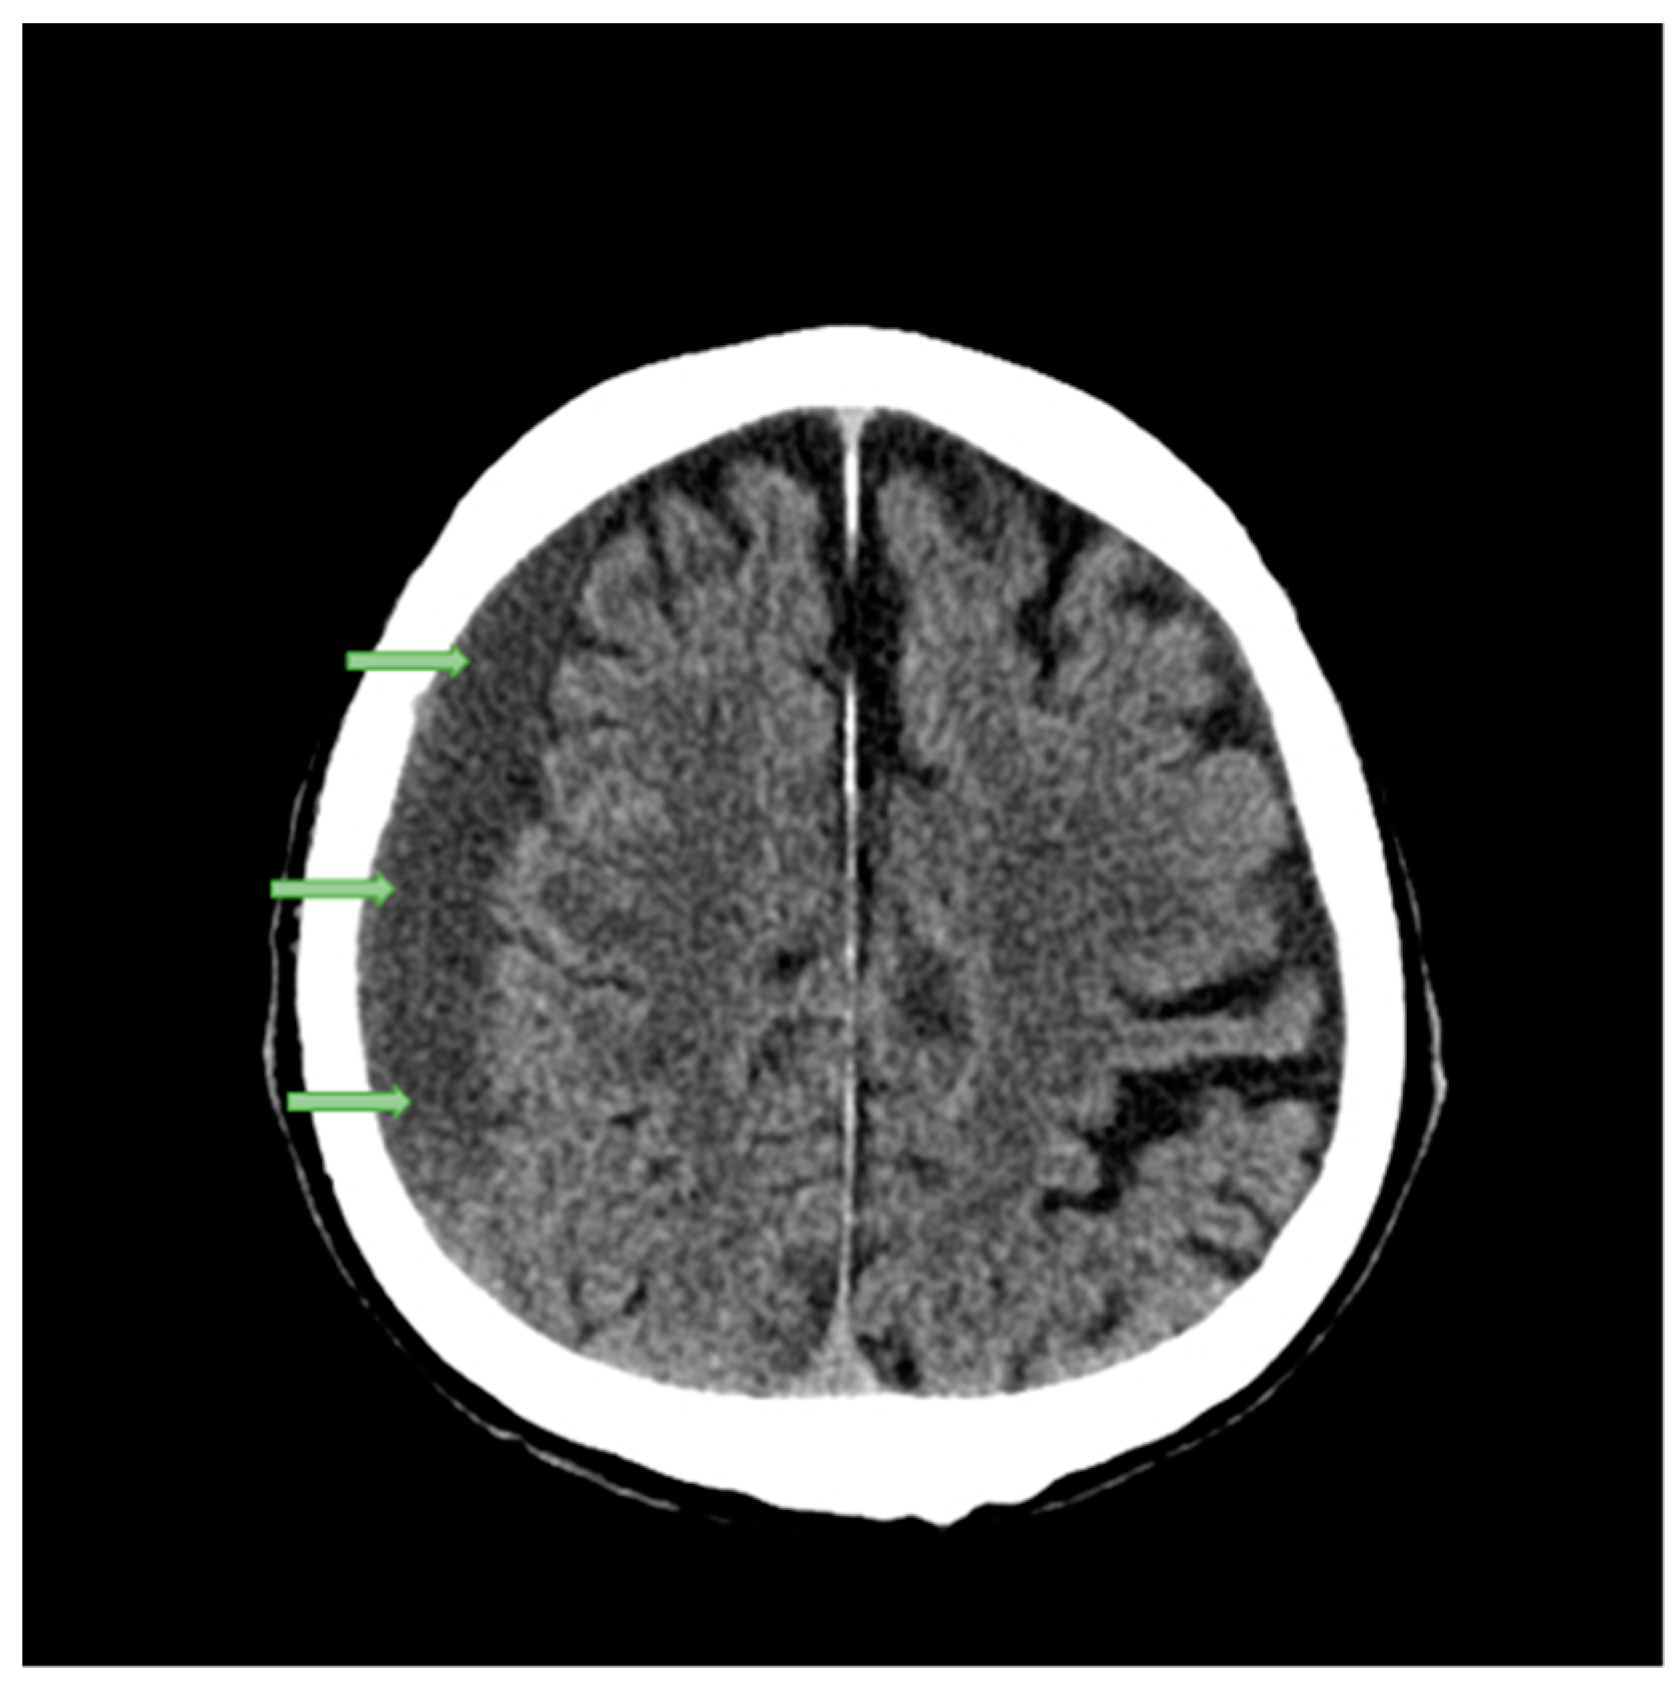

2.1. Case Studies